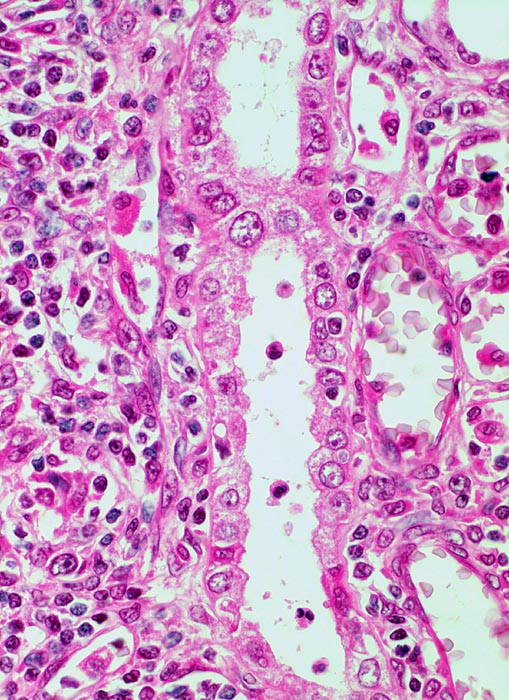

akute Transplantatverwerfung: leichte Tubulitis

Leichte Tubulitis mit weniger als 4 mononukleären Entzündungszellen pro 10 Tubuluszellen. Im angrenzenden Interstitium ebenfalls gemischtes mononukleäres Infiltrat mit Lymphozyten, Immunoblasten mit grossem zentralem Nukleolus und Histiozyten mit bohnenförmigen Kernen.

Gemäss der Banff Klassifikation wird die Tubulitis quantifiziert mit einem Score:

t0 = keine mononukleären Zellen im Tubulus

t1 = 1 bis 4 Entzündugnszellen pro tubulärer Querschnitt oder pro 10 Tubuluszellen

t2 = 5 bis 10 Entzündugnszellen pro tubulärer Querschnitt

t3 = >10 Entzündugnszellen pro tubulärer Querschnitt